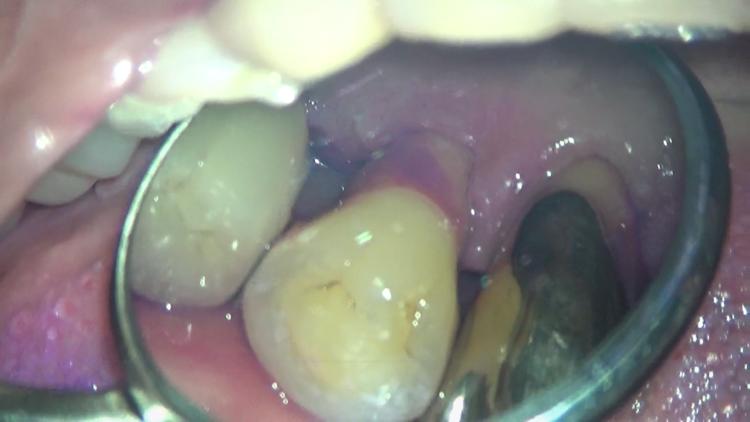

歯周病により歯槽骨の吸収、それに伴う歯肉の退縮がみられるケースです。

全体的に良く磨いてくださっていますが、一か所だけ極端にプラークが残ってしまっています。

これは、左下の裏側です。プラークの染め出しを行ってみると、ベッタリと紫色に染まっています。